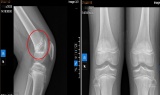

Cảnh báo bệnh lý dễ bị bỏ qua khiến nhiều trẻ đau gối kéo dài khi vận động mạnh -